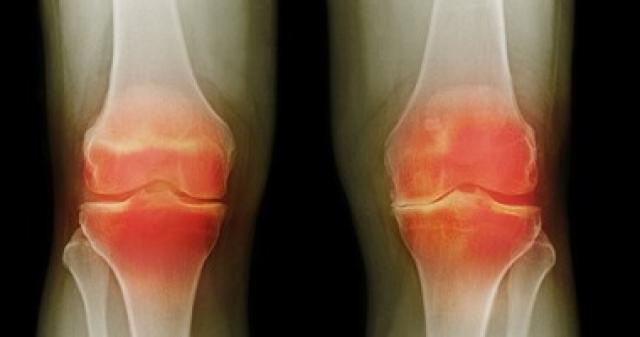

وحسبما ذكر موقع "intermountain healthcare"، فإن النساء تصاب بالتهاب المفاصل أكثر من الرجال، بسبب أن لديهن مرونة أكثر في الأوتار، ولذلك يؤثر الالتهاب على مفاصل الفخذ عند الرجل، بينما يؤثر على مفاصل اليدين والركبة والفخذين عند النساء.

وتعد زيادة الوزن وسيلة للإصابة بالتهاب المفاصل أيضًا، ولأن السمنة أكثر شيوعًا بين النساء عن الرجال، فإن ذلك يضغط على مفاصل الركبة ويؤدي إلى تآكل الغضاريف مع التقدم في السن، وبالتالي تحدث الإصابة بالتهاب المفاصل.